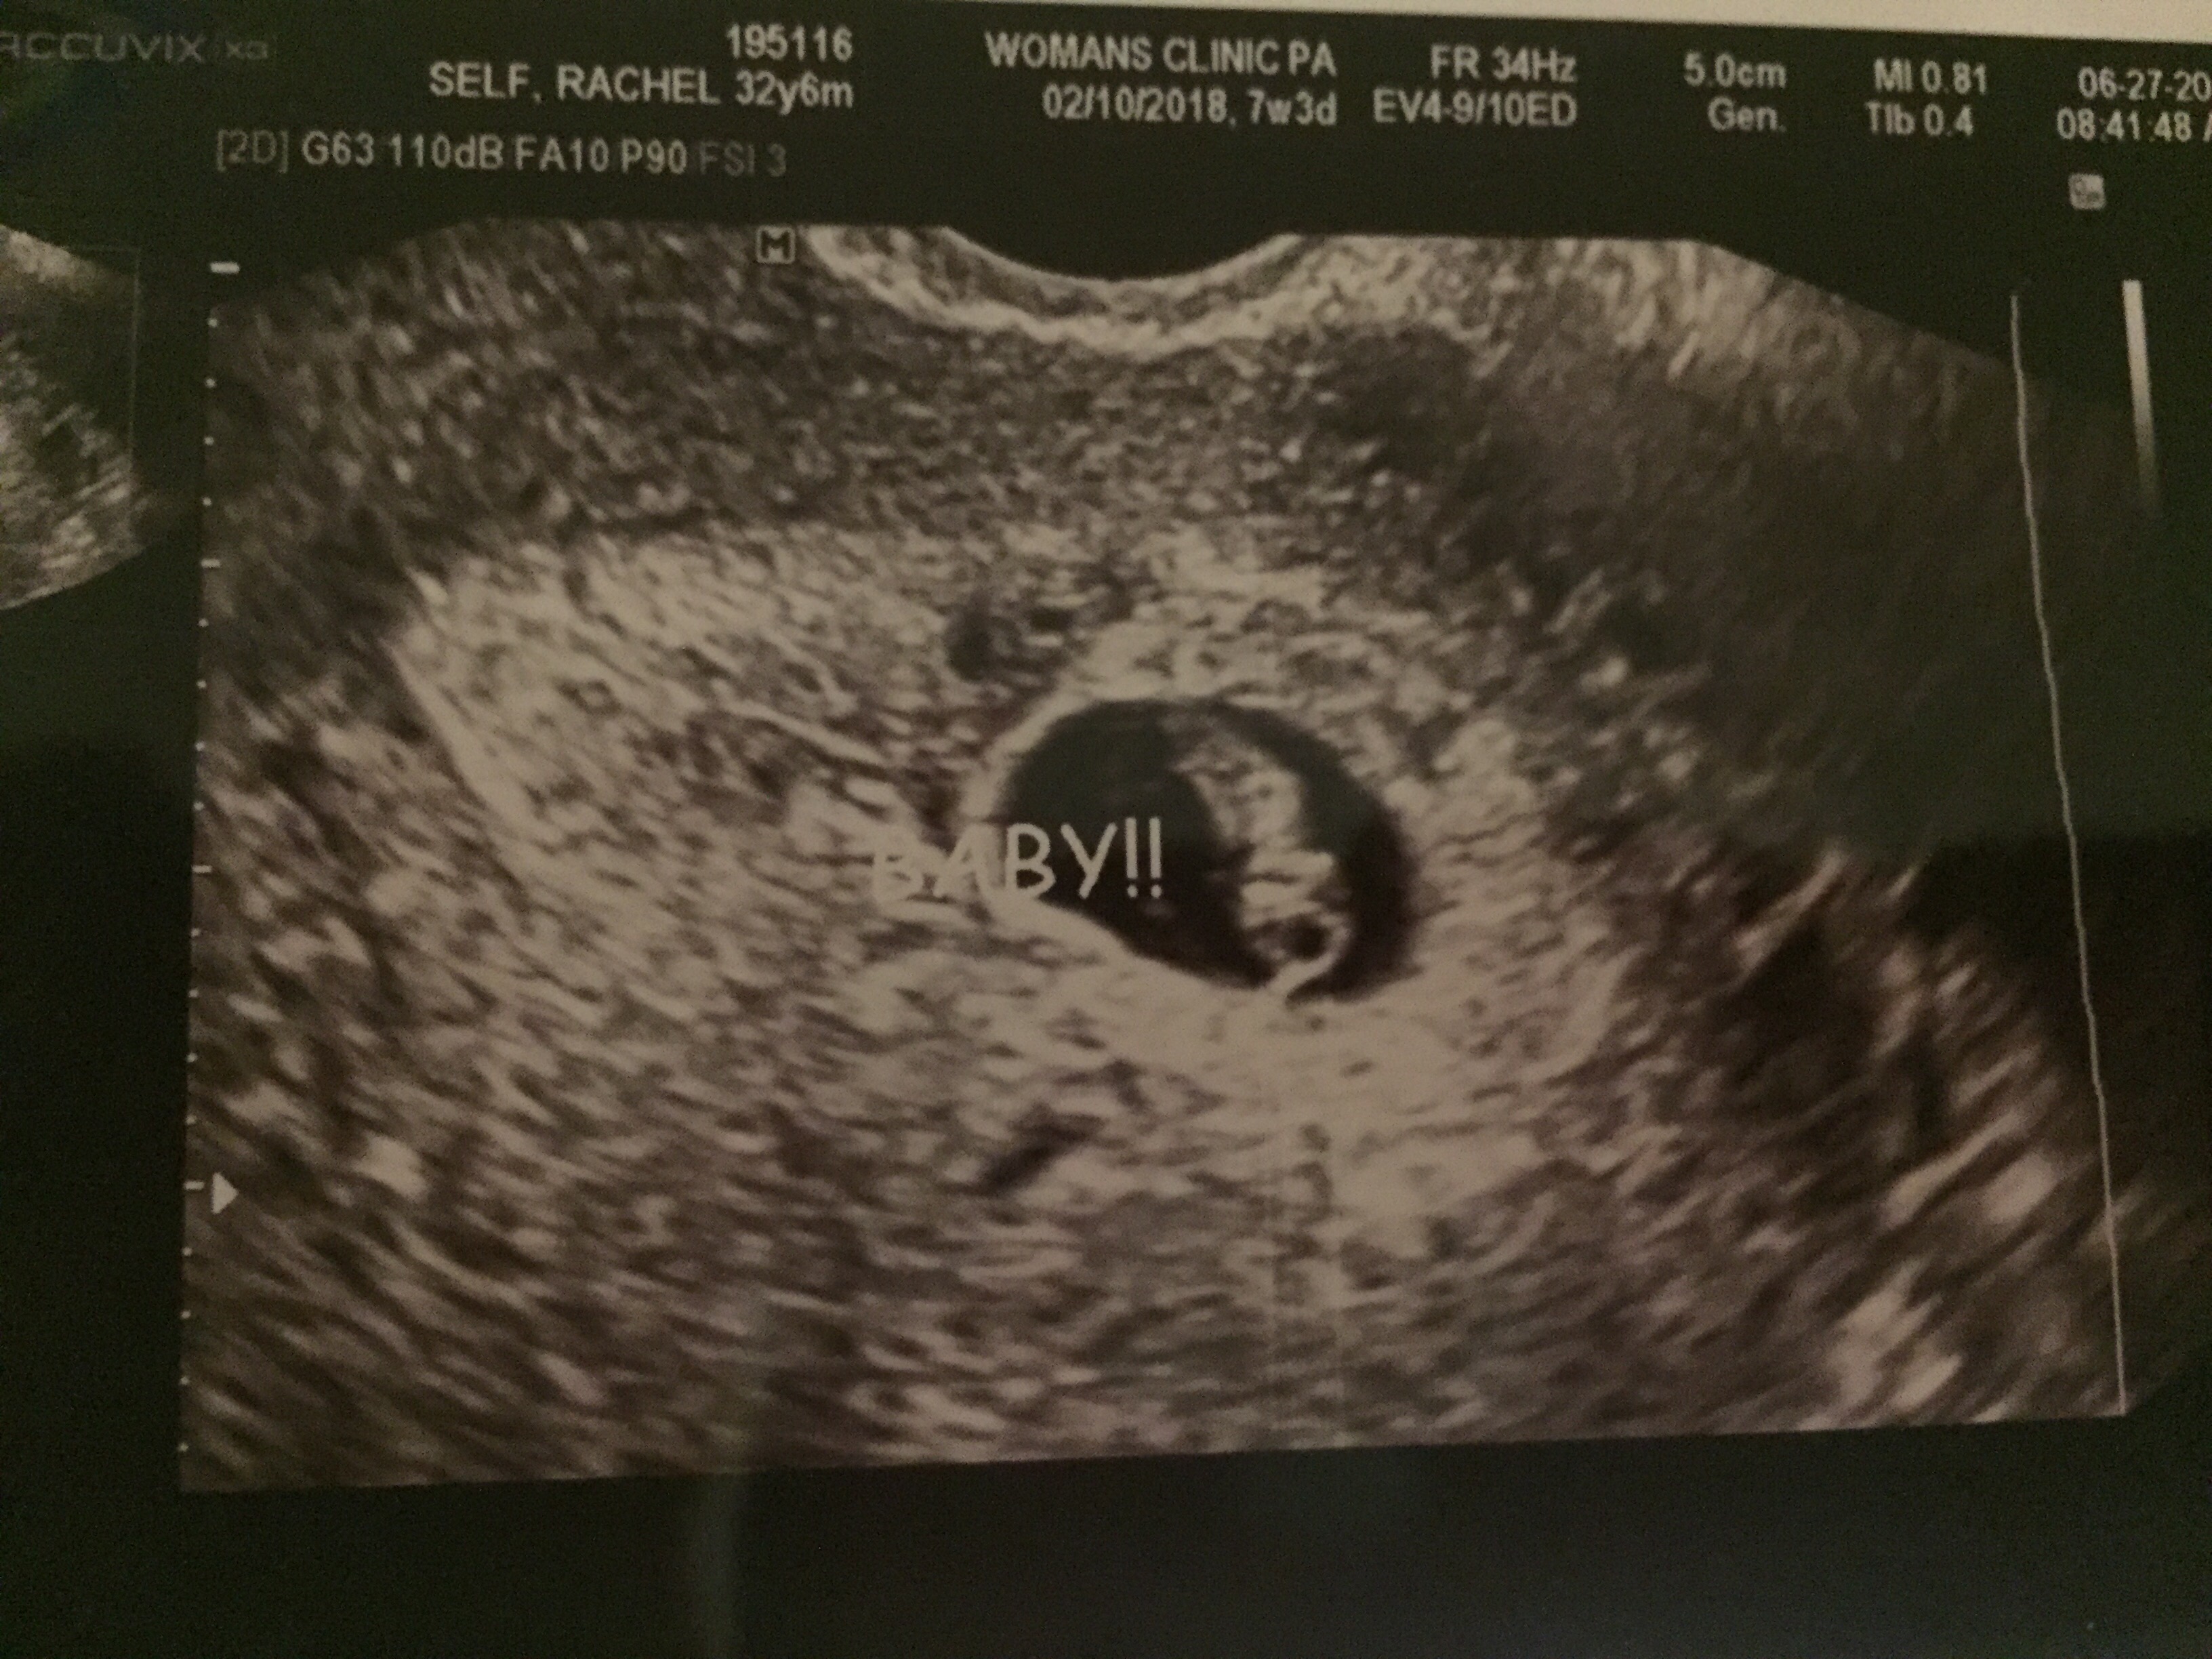

I’m guessing you caught the word “was” in that last sentence. I was pregnant. I’m not anymore. The month of June was joyous for our family. We traveled and saw friends and family, we hosted VBS at our church, and we celebrated a new life that was growing in my womb. And I was nauseous, but we’ll just ignore that for this post.

With July came my youngest son’s second birthday and a huge community celebration for Independence Day. The first few days were fun, but something was off. I knew it. So on Thursday, July 6 I called my OB office. I felt a little silly but I just had a bad feeling. I knew I would be too worried to wait three weeks for my next appointment. So I called, and they let me come in just for “peace of mind.” Only when I got there, I found out what I had suspected. The baby no longer had a heartbeat.